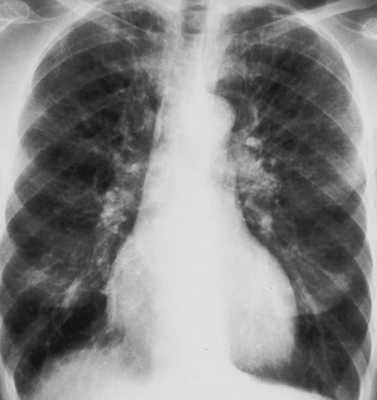

Биохимические показатели венозной крови характеризуются гипоальбуминемией, повышением свертывающих факторов, нарастанием трансаминаз и билирубина. При рентгенографии легких на периферии выявляются диффузные множественные тени (симптом "снежной бури"), снижение прозрачности легочной ткани, плевральный выпот обычно отсутствует.

Выполняется рентгенография органов грудной клетки для выявления пневмоторакса или пневмомедиастенума (наличие контрастной полосы вдоль контура сердца). Если рентгенография органов грудной клетки не выявляет нарушений, но клинические данные заставляют подозревать их, показана диагностическая КТ органов грудной клетки, которая более чувствительна по сравнению со стандартной рентгенографией. Ультразвуковое исследование также может использоваться для быстрой диагностики пневмоторакса у кровати пациента. Пневмоперитонеум без разрыва внутреннего органа следует подозревать в том случае, когда он присутствует без наличия перитонеальных признаков.

- III (стадия дыхательной недостаточности) - спустя 12-24 часа после воздействия стрессового фактора. Клокочущее дыхание с выделением пенистой розовой мокроты, нарастающая гипоксемия и гиперкапния, поверхностное дыхание, увеличение центрального венозного и снижение артериального давления. По всей поверхности легких выслушиваются влажные, множественные хрипы различного калибра. На рентгенограммах определяется слияние очаговых теней. В этой стадии происходит образование гиалиновых мембран, заполнение альвеол фибрином, экссудатом, распадающимися кровяными тельцами, поражение эндотелия капилляров с образованием кровоизлияний и микроателектазов.